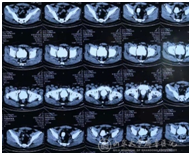

图5、6:术后随访双肾无积水